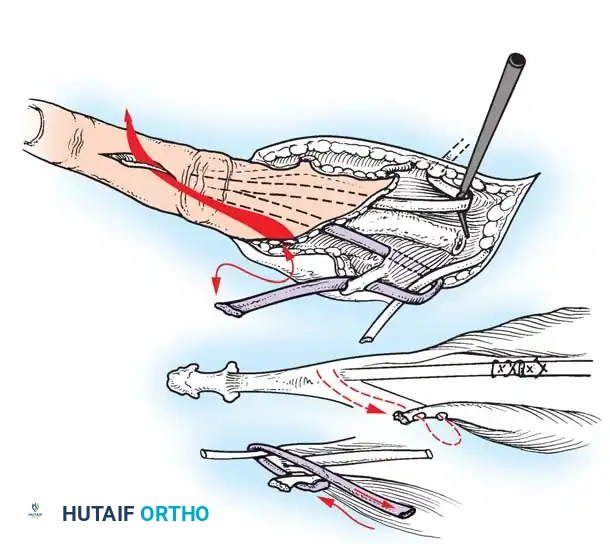

- Incision: Make a curved, horseshoe-shaped incision around the dorsal, radial, and volar aspects of the base of the thumb.

- Flap Elevation: Undermine the skin distally, staying strictly superficial to the main venous drainage network to prevent venous congestion and subsequent flap necrosis. Continue undermining until a hollow, thimble-like flap has been elevated and slipped off the end of the bony stump. The blood supply to this flap is maintained via the arborization of vessels around the base of the index finger in the thumb web.